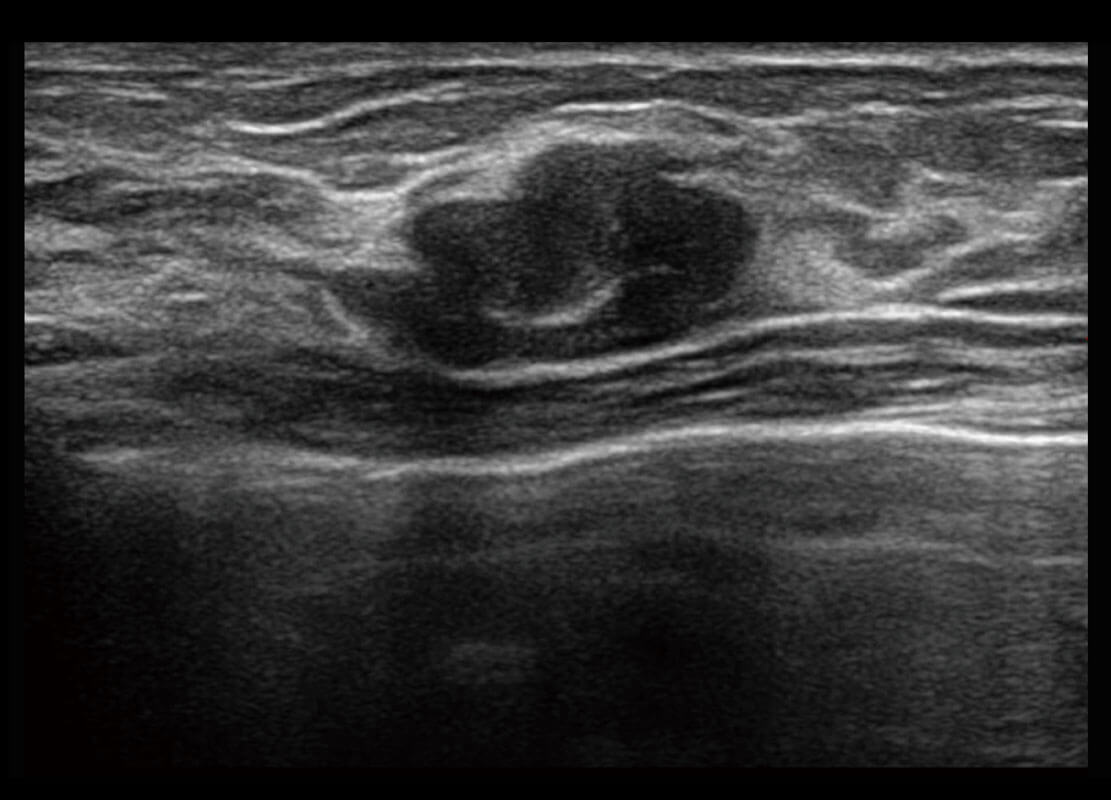

• 乳腺导管癌

• 乳腺癌显微血流